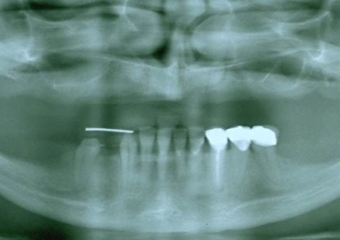

Perfil inicial